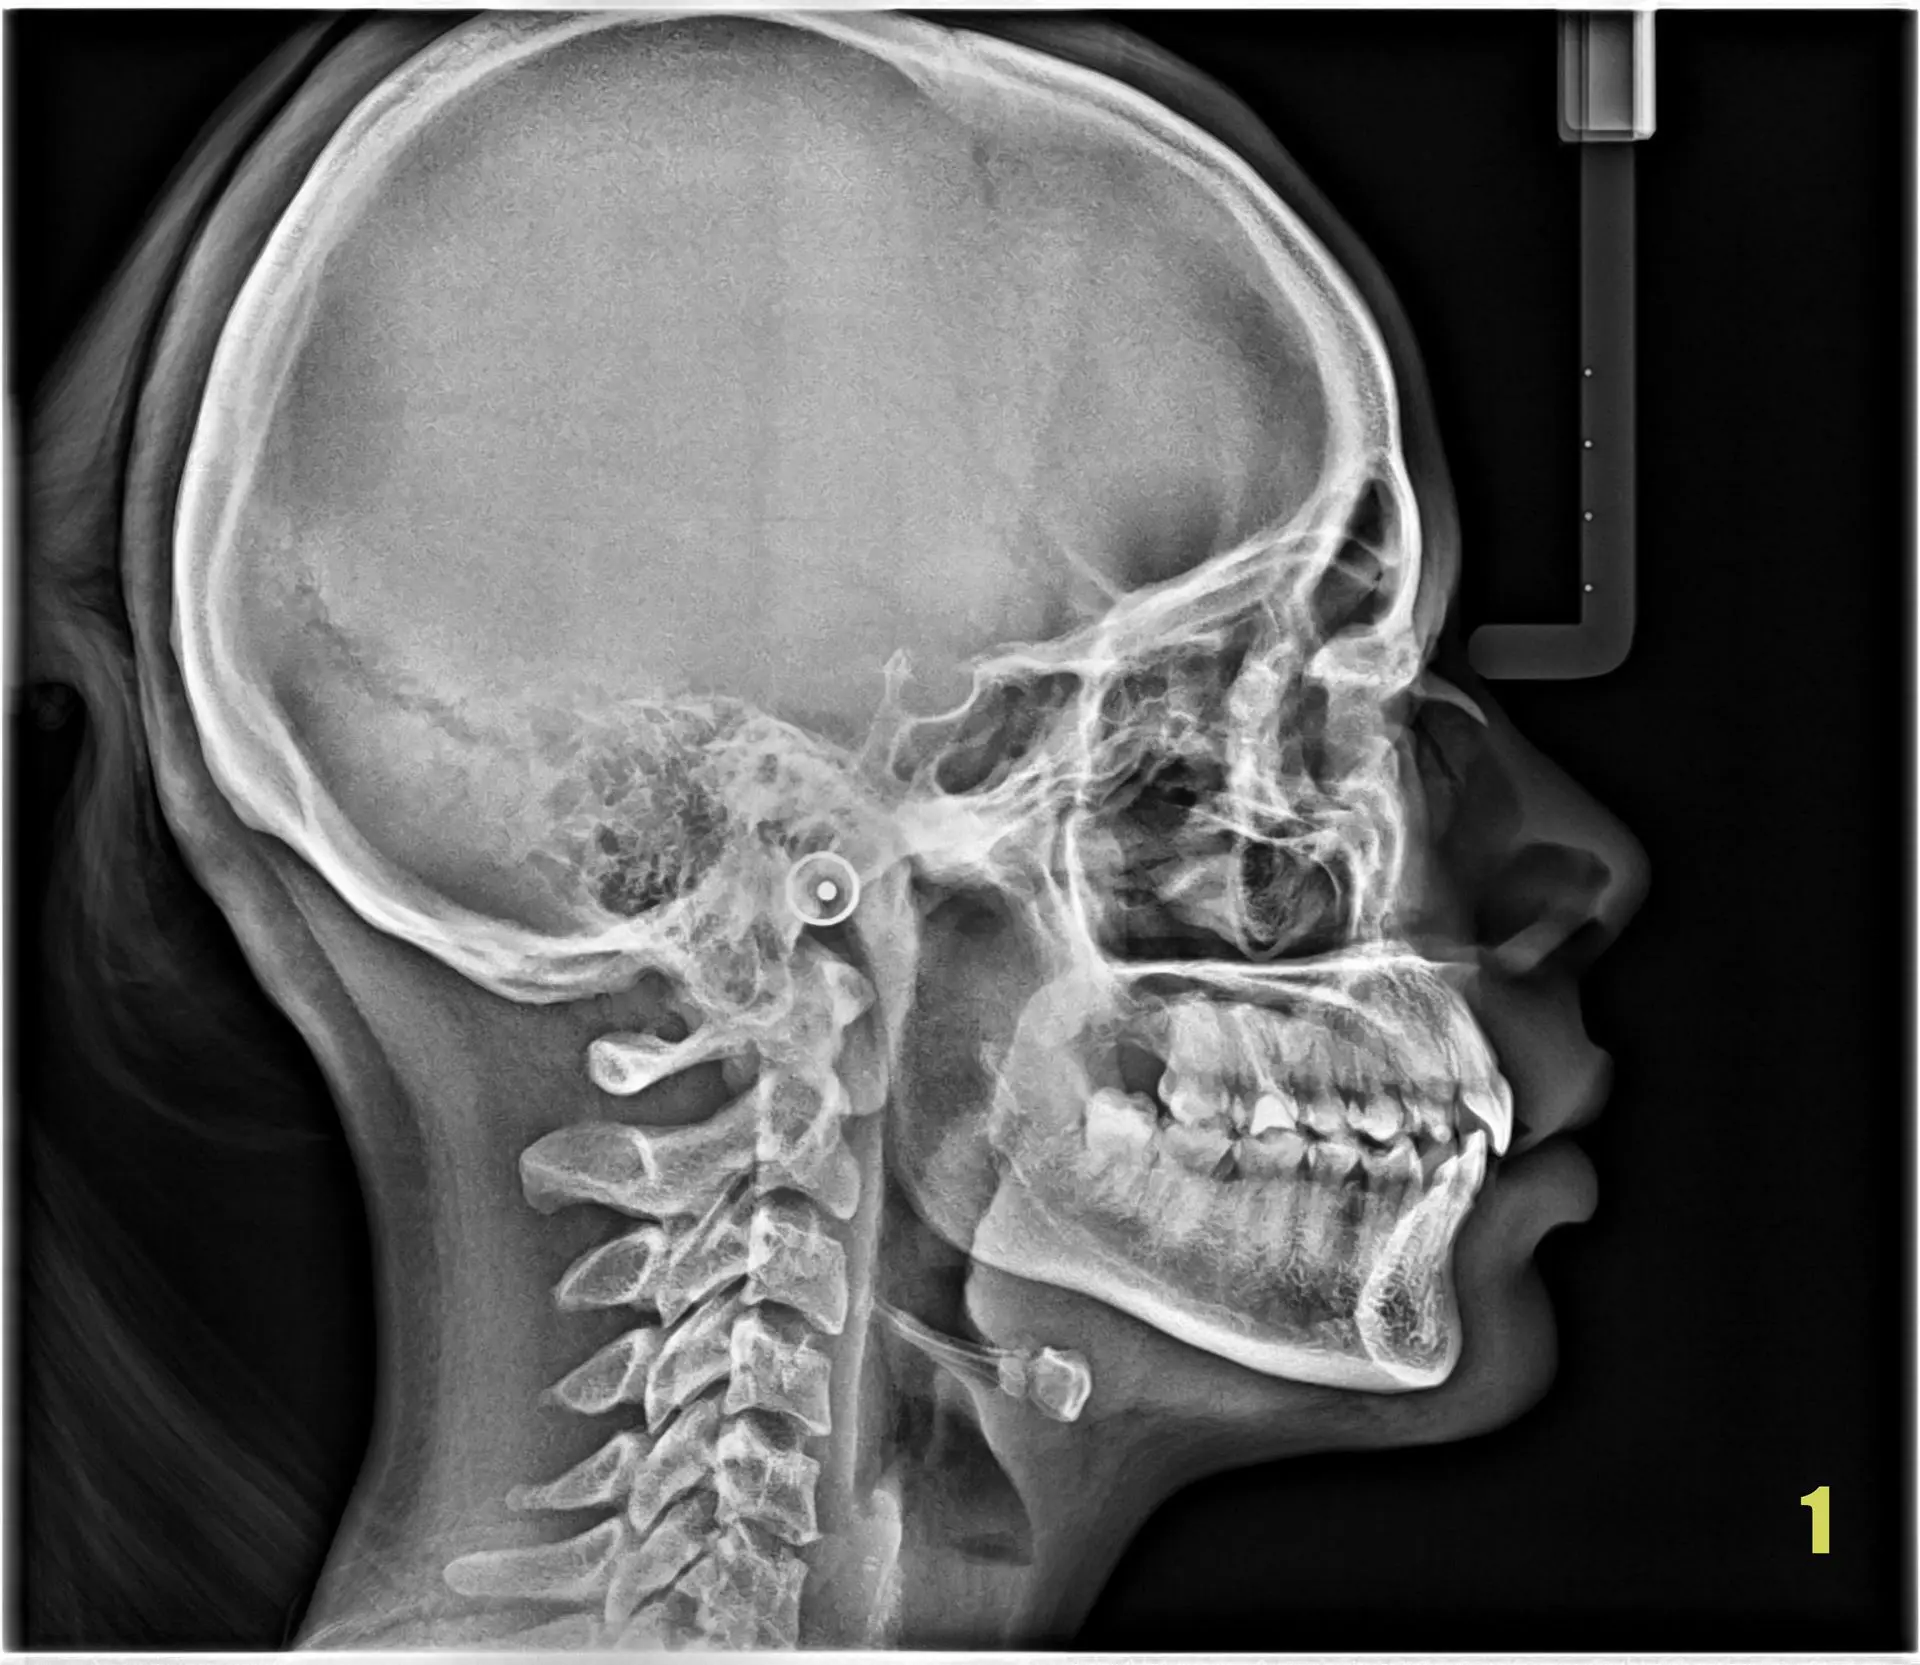

Paciente: Femenino, 20 años.

Motivo de consulta: Fase de Diagnóstico Complementario

Estudio solicitado: Tomografía Cone Beam de Superior completo.

La paciente concurre a realizarse una telerradiografía de perfil (Imagen 01) para iniciar tratamiento de ortodoncia, 30 días después concurre nuevamente con las ortodoncias puestas para realizarse una tomografía para complementar el tratamiento, donde se encontraron varios hallazgos.(Imagen 02) Los cuales se describen con la letra "N" contabilizando 3 en total en el maxilar inferior y ocupando lugares para la normal erupcion de los caninos superiores